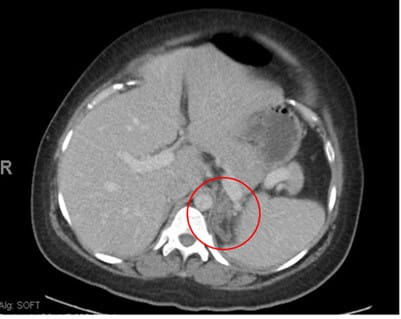

The following day, the patient developed hypoxia and tachycardia. A follow-up CTa was remarkable for the development of a new right adrenal hemorrhage (see Image 4).

Image 4: CT Angiogram remarkable for increased soft tissue bulkiness and partial obliteration of fat planes within the region of the right adrenal gland with Hounsfield units measuring 56 suspicious for new right adrenal hemorrhage.